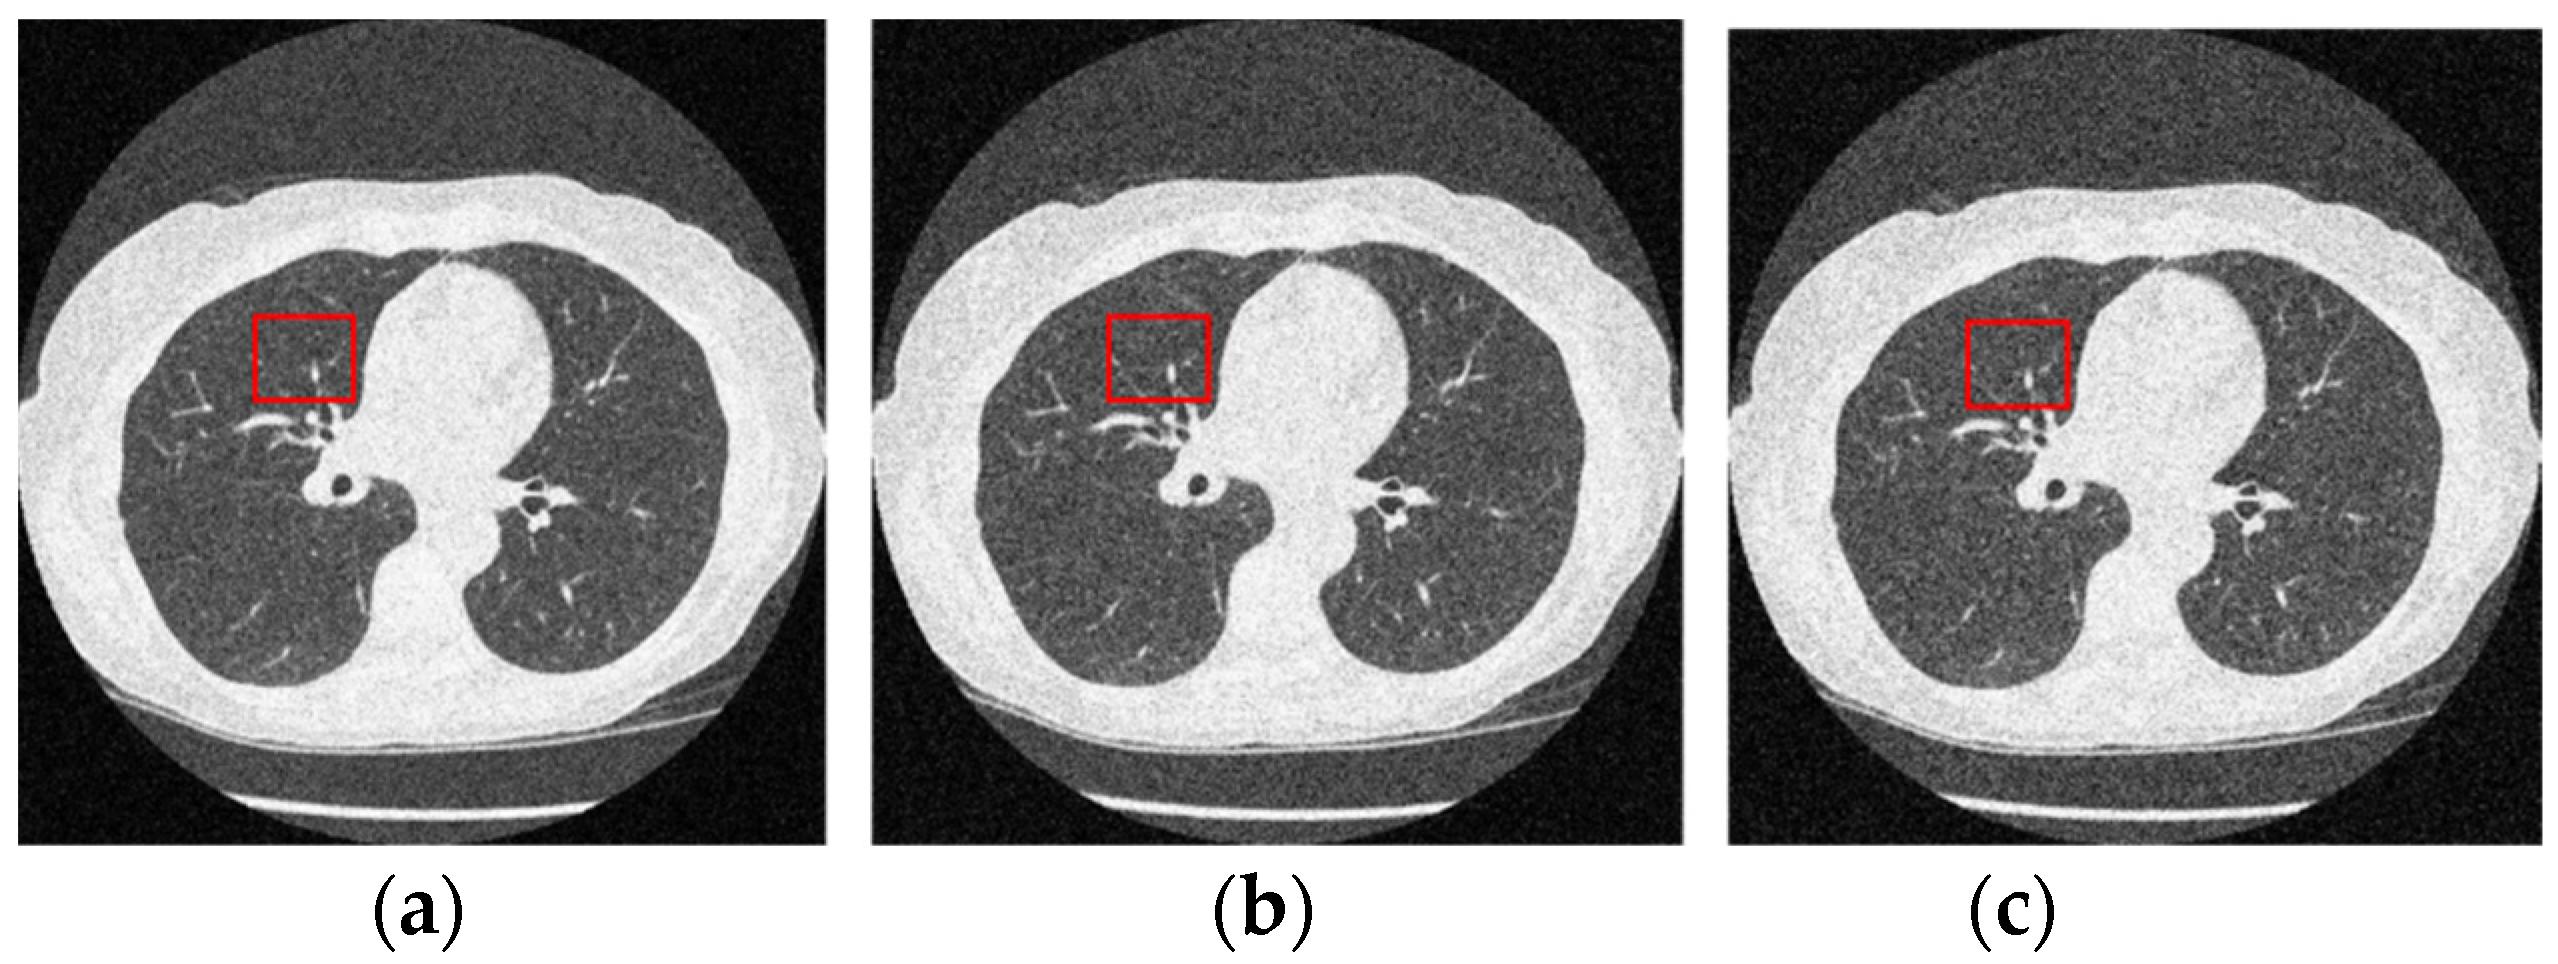

Figure 12 and Figure 13 analyze the region of 45 × 45 that has been considered to be the upper right area of the center in a region containing all types of details, including edges, shade gradient, and extremities, in contrast values. This region was mapped in the same area for all the noisy and denoised CT images using built-in MATLAB functions. Post this, magnification shows the edge reconstruction and contrast restorative properties of this framework in grandiose detail in Figure 14. The white regions of details are visible with a high level of clarity in the denoised CT images in Figure 14. The Gaussian noise is also clearly visible in the magnified view, as seen in Figure 14a–c. The recovery from Figure 14c is beyond the capability of any human expert, which is done flawlessly by the system.

Figure 12.

Noisy CT images with various noise variance levels (a) 1% Gaussian noise, (b) 1.5% Gaussian noise, and (c) 2% Gaussian noise.

Figure 13.

Denoised CT images generated via proposed technique: Marked region used for zooming analysis; (a) denoised on 1% Gaussian noise, (b) denoised on 1.5% Gaussian noise, and (c) denoised on 2% Gaussian noise.

Figure 14.

Comparison of the marked region from noisy and denoised CT images: Zooming analysis of the marked region. (a) 1% Gaussian noise, (b) 1.5% Gaussian noise, and (c) 2% Gaussian noise.